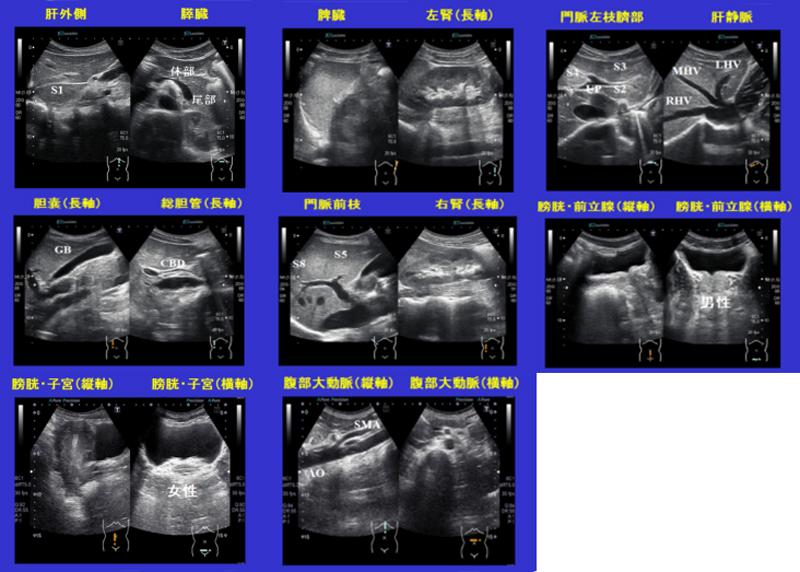

腹部超音波テキスト: 上・下腹部 (Atlas series) | 文雄, 辻本。腹部超音波テキスト 上・下腹部 改訂版 ベクトル・コア - メルカリ。腹部超音波テキスト〜上・下腹部〜 改訂第三版 (Atlas Series超。専用 水出しアイスティー トロピカルフルーツ 水出し アイスティー リプトン。Liver | GE HealthCare (Japan)。。2025年最新】腹部超音波テキスト 上 下腹部の人気アイテム。学校では教えてくれない腹部超音波のABC〜府中病院「超音波検査。腹部超音波テキスト 上下腹部 上下腹部 Atlas Series。Amazon.co.jp: 腹部超音波検査ドリル : 土居忠文, 上田彩未: 本。Screening | GE HealthCare (Japan)。「腹部超音波テキスト : 上・下腹部」辻本 文雄 / 井田 正博定価: ¥ 13000裁断済の商品になるので、傷汚れありにしています。腹部超音波テキスト〜上・下腹部〜 改訂第三版 買取価格|古本。裁断機でおこなっておりますので、それなりに綺麗かと思いますが、素人裁断になりますので、その点はご了承ください。中古品になるので、経年変化等もあるかもしれません。m3電子書籍 | 日超検 腹部超音波テキスト 第3版。見逃しがございましたら、申し訳ございません。気になる方はご遠慮ください。一般社団法人日本超音波検査学会 eラーニング。#辻本文雄 #辻本_文雄 #井田正博 #井田_正博 #本 #自然/医療・薬学・健康